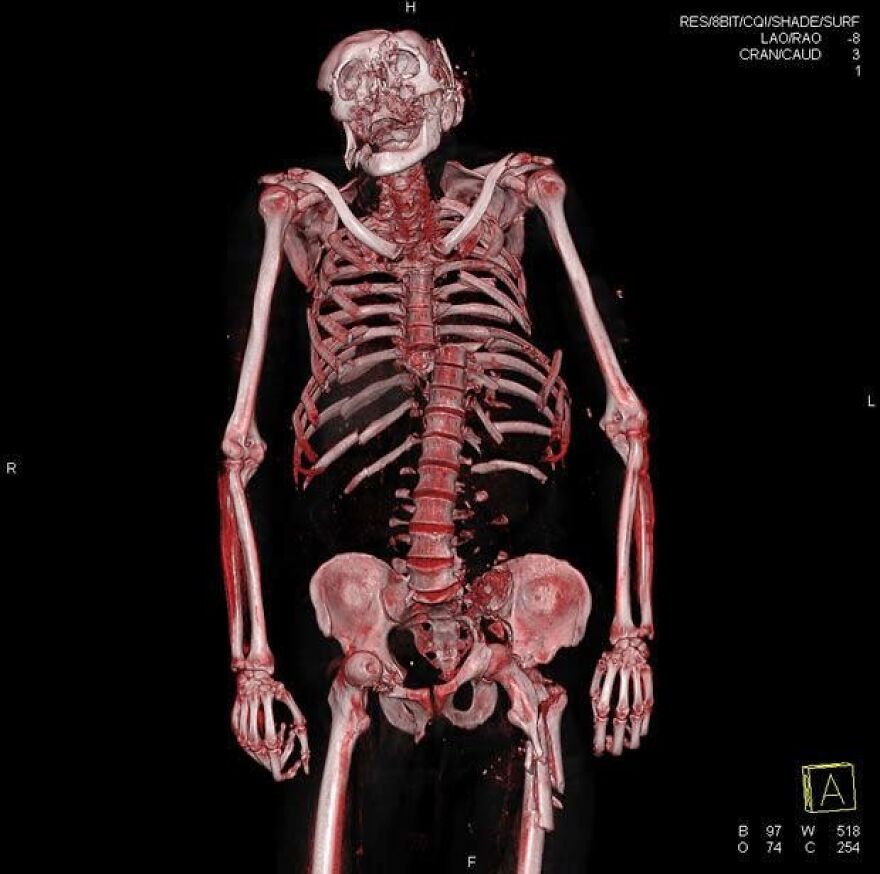

Skull of a person who had skeletal cancer